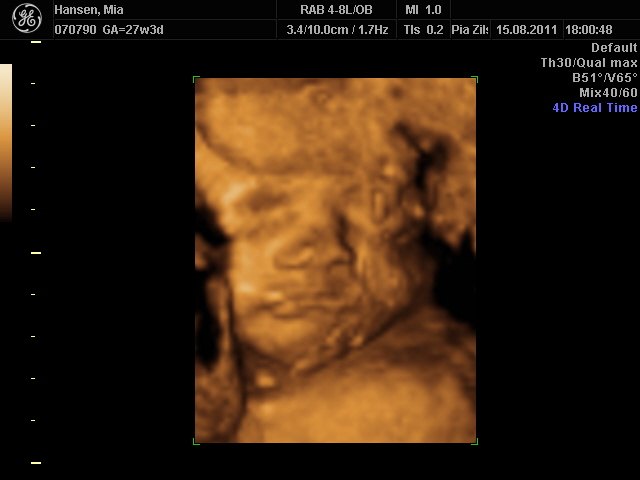

Fantastisk oplevelse. Lillepigen er bare så fin  en rigtig putte-pige

her kommer lidt billeder

Mia 27+3